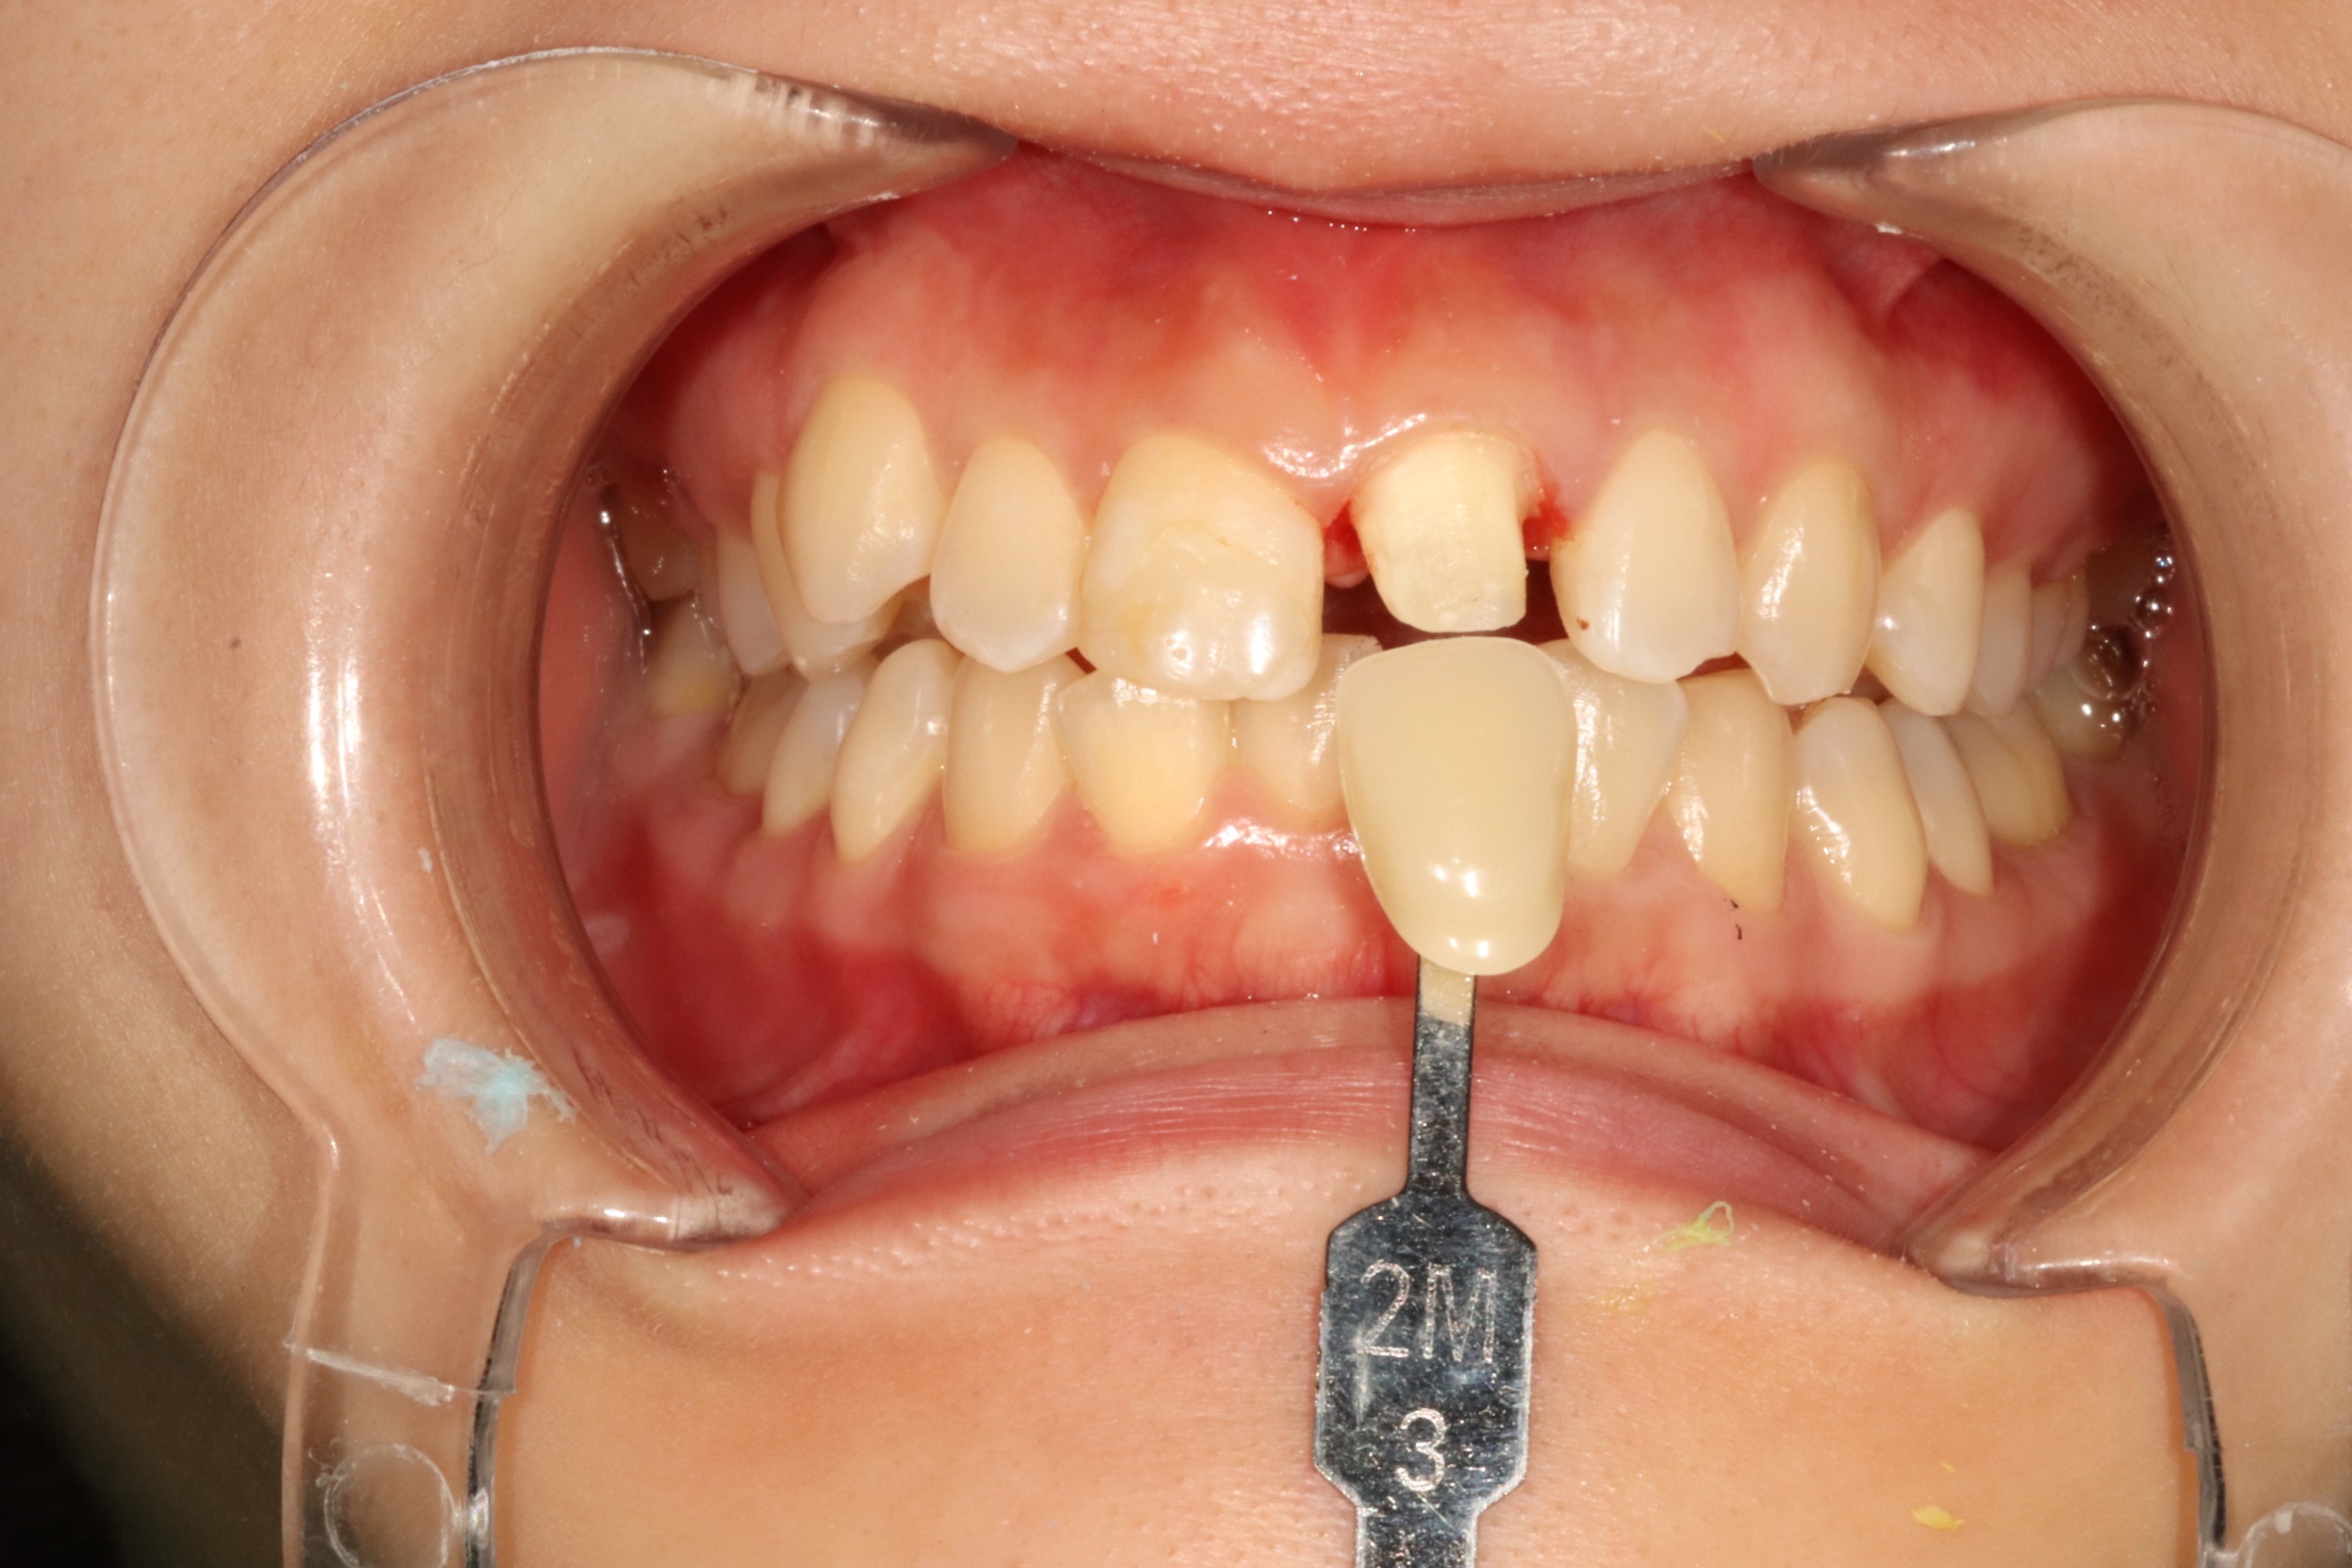

신경치료 후 크라운

Before

After

근관치료 후 치아 보호를 위한 크라운